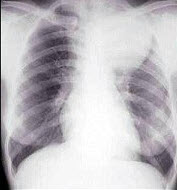

[单选题]女,25岁,胸背痛半月余,胸片如图,最可能的诊断为()A . 左上肺不张B . 左上肺炎C . 纵隔肿瘤D . 左上肺癌E . 左上肺炎性假瘤